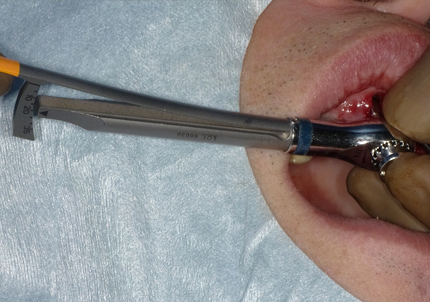

7.インプラントの型どり

インプレッションコーピングを用いての型どり

➡インプラントの“正確な位置”を模型に再現するための型取り専用パーツのこと。これを付けて印象採得することで、被せ物が口の中でぴったり合う精密な補綴物を作ることができます。